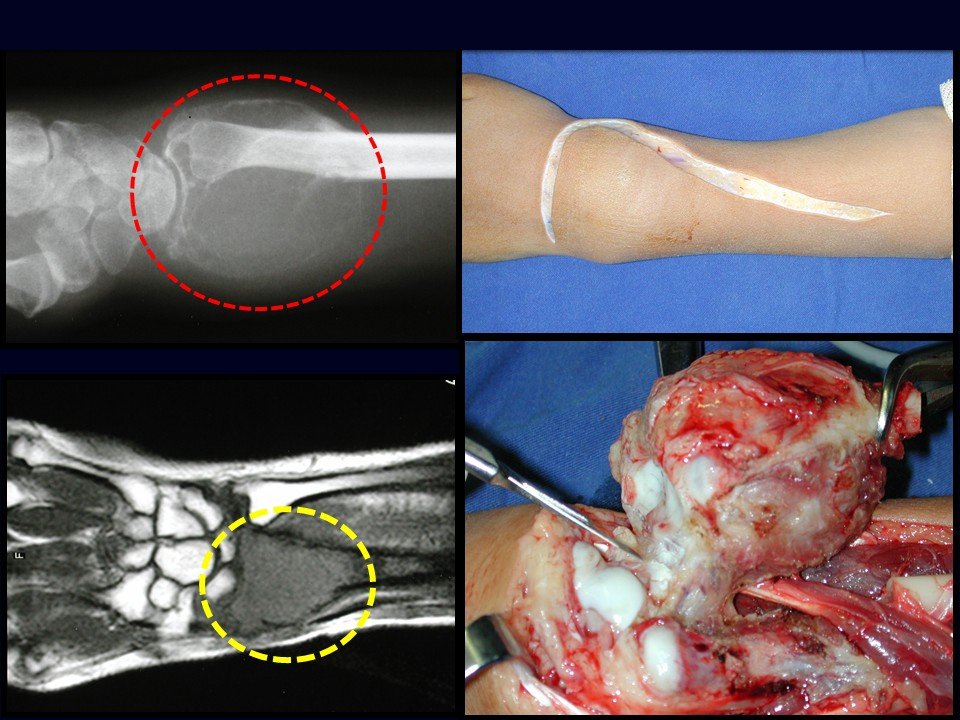

Figura 10: Tumor de células gigantes do rádio, com grande insuflação e agressividade local. O estudo da ressonância permite verificar que a lesão não invade os tecidos moles, apenas deslocando os tendões. Isso possibilita a ressecção oncológica do tumor, que foi operado por meio de uma ampla incisão dorsal, iniciando na apófise da ulna, seguindo em direção à estiloide do rádio e curvando-se proximalmente. Abrimos a articulação do punho, liberamos os tendões de suas polias e removemos o tumor.